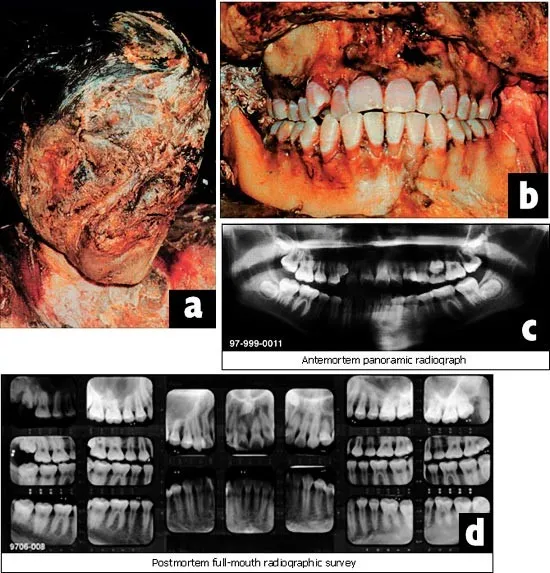

- Principle: Systematic comparison of ante-mortem (AM) dental data (charts, X-rays, clinical photographs, dental casts, retainers, aligners) with post-mortem (PM) dental findings from victims.

- Radiographic: Superimposition of AM/PM X-rays (IOPA, OPG), CBCT for 3D reconstruction.

- Dental ID compares ante-mortem (AM) records with post-mortem (PM) findings.

- Radiographs are vital for comparing trabecular patterns, root morphology, and unerupted teeth.